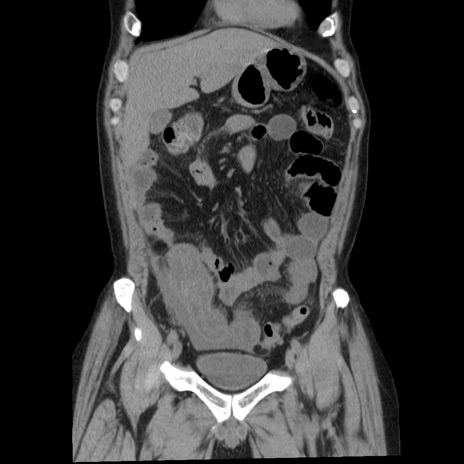

症例29(冠状断像)

【症例】40歳代男性

【現病歴】2日前から胃痛あり。徐々に周期的な激痛に変化した。本日になっても激痛があるため受診。

【身体所見】意識清明、BT 38-39℃台あり、腹部:膨満、やや硬、右下腹部に圧痛あり。

【データ】WBC 8500、CRP 23.26